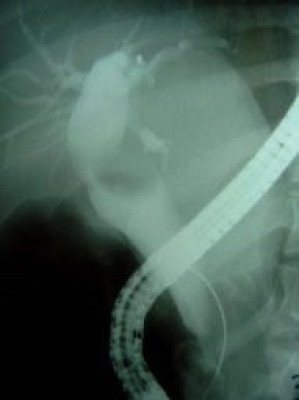

Cálculo gigante y divertículo duodenal ERCP

Envíado por Dr. Carlos Miguel Zavaleta Consuegra